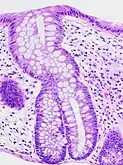

| A micrograph demonstrating cryptitis, a microscopic correlate of colitis. H&E stain. | |

An important investigation in the assessment of colitis is biopsy for histopathology. A very small piece of tissue (usually about 2mm) is removed from the bowel mucosa during endoscopy and examined under the microscope by a histopathologist. A biopsy report generally does not state the diagnosis, but should state any presence of chronic colitis, give an indication of disease activity, as well as state the presence of any epithelial damage (erosions and ulcerations).[4]

Histopathology findings generally associated with chronic colitis include:[4]

Crypt degeneration

Crypt degeneration Crypt branching and other architectural distortions

Crypt branching and other architectural distortions Paneth cell (pictured) or gastric metaplasia (only applies in the left colon and rectum)

Paneth cell (pictured) or gastric metaplasia (only applies in the left colon and rectum)

Other findings include basal plasmacytosis and mucin depletion.[4] Histopathology findings generally associated with active colitis include:[4]

Neutrophilic cryptitis (neutrophils within crypt epithelium)

Neutrophilic cryptitis (neutrophils within crypt epithelium) Crypt abscesses (luminal neutrophilic aggregates)

Crypt abscesses (luminal neutrophilic aggregates) Gland destruction

Gland destruction Ulceration (seen here as absence of epithelium, and granulation tissue with many fibroblasts)

Ulceration (seen here as absence of epithelium, and granulation tissue with many fibroblasts)